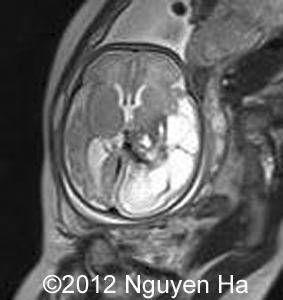

Figures 16-21:Prenatal MRI.

Figure 16-21:MRI after the first ultrasound 4 days suggesting a hematoma on the left side of the brain.